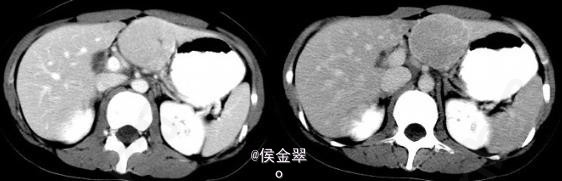

患者,女,30岁,因反复上腹部疼痛不适1年前来就诊。

患者查体发现上腹疼痛不适,其余正常 辅查CT:平扫为低密度占位,增强后期出现快速强化。

肝脏局灶性结节性增生 处理:观察随访如肿瘤生长则切除